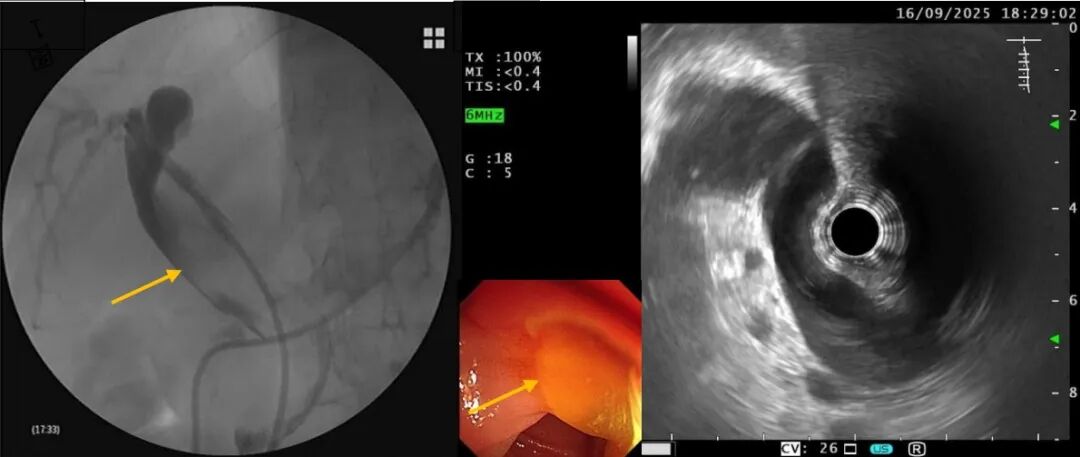

超声内镜显示:肝内外胆管扩张,胆管里充满了黏液。初步判断可能是“胆管内乳头状黏液性肿瘤(IPMN-B)”,但肿瘤究竟藏在哪?

鼻胆管造影见胆管内大量充盈缺损影(箭头所示),超声内镜见肝内外胆管增宽;乳头开口大量黏液(箭头所示)

为了明确诊断,ERCP治疗团队使用了胆道子镜直视进入胆管内进行观察,视野却被大量黏液阻挡。治疗团队没有放弃,他们先用球囊清理胆道为子镜“开路”。再次进入时,终于在左肝内胆管发现了匍匐生长的乳头状病变。子镜直视下,医生精准取样送往病理科。病理结果揭晓:胆管腺瘤,导致黄疸的“真凶”终于被揪出!